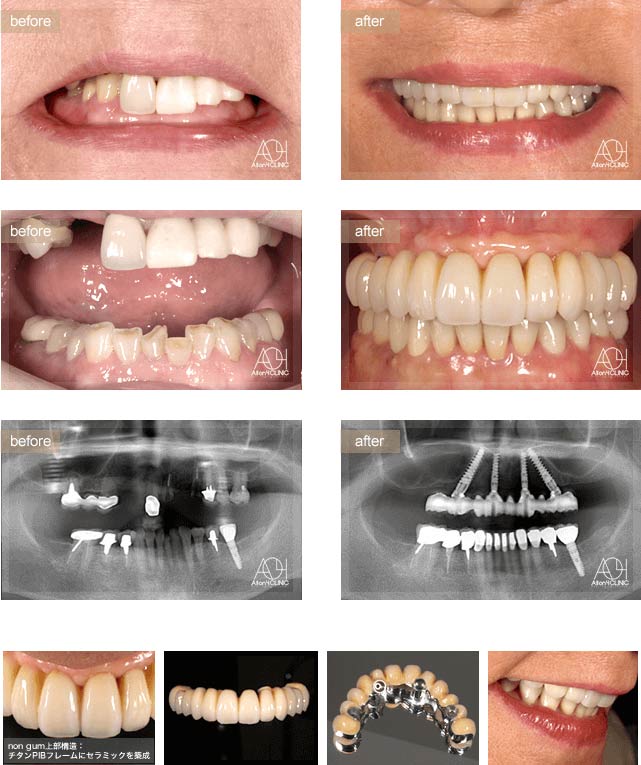

Treatment : All-on-4 non gum

- Upper All-on-4

- Lower implant

Age : 42 Sex : 女 Y.R

| 主訴 | 歯がボロボロなのは分かっているが、時間的な余裕が無いことと歯科に対する恐怖心から、悪いままの状態を放置してしまった。人前でおもいっきり笑いたいので意を決して来院。 |

| 治療内容 | ガイデッドサージェリーにてインプラント埋入。歯槽骨が残っていたため歯冠形態のみ(ガム無し)の補綴 |

| 治療費(総額) | ¥3,500,000(税抜) 『モニター割引適用』 |

| リスク | 治療後の口腔管理が不適切な場合、埋入したインプラント周囲に感染・炎症を起こし、脱落する可能性がございます。 |